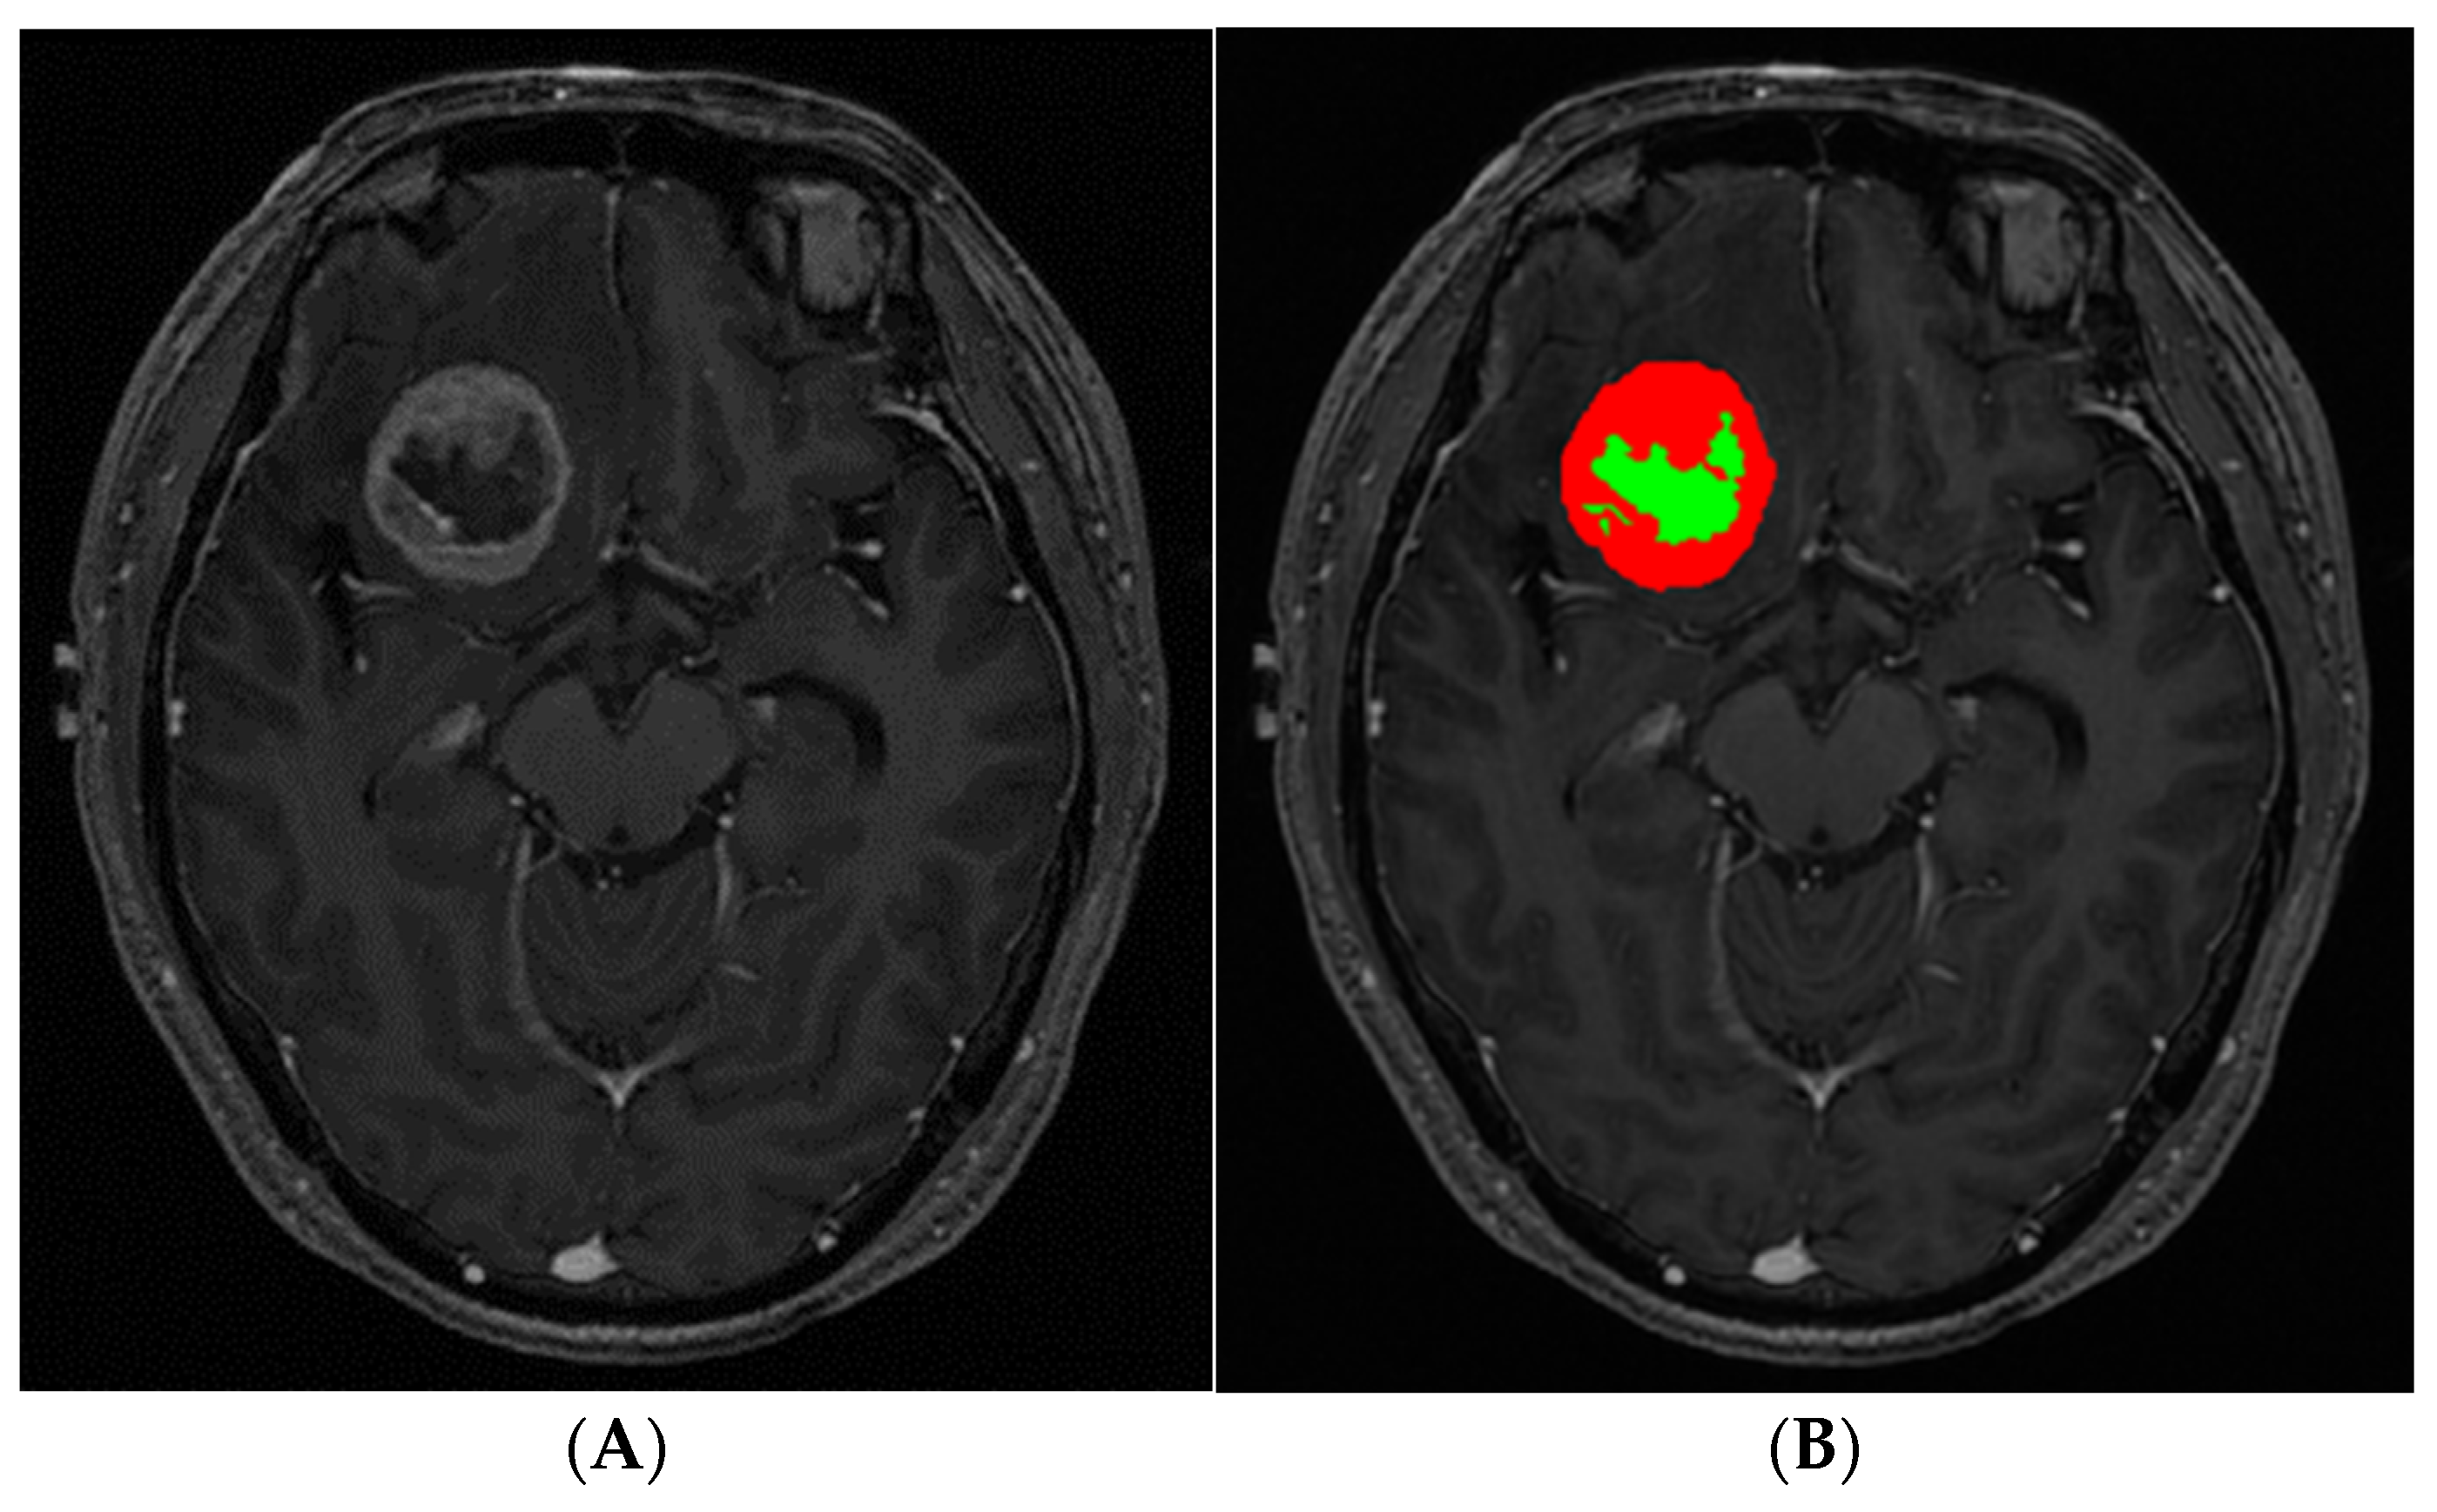

2.2. MRI

2.3. Image Postprocessing and Analysis